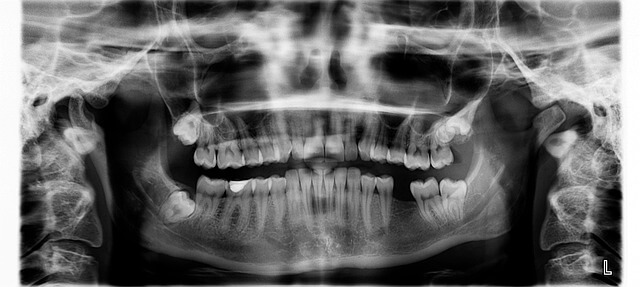

* 우리가 흔히 무심코 넘기는 잇몸의 피, 그 시작이 바로 치주염 증상일 수 있습니다. * 치주염은 단순히 잇몸에서 피가 나는 게 아니라 치아 뿌리까지 손상시키며, 결국 치아 상실이라는 큰 결과로 이어질 수 있습니다. * 실제로 많은 사람들이 아침에 일어나 입안이 텁텁하거나, 양치 후에도 잦은 출혈을 경험하면서도 대수롭지 않게 여깁니다. * 하지만 이렇게 방치된 치주염은 입 냄새나 씹기 어려움 같은 생활 불편을 만들고, 점점 삶의 질을 떨어뜨립니다. * 이런 고민 하셨다면, 지금이 바로 치주염 증상을 돌아보고 제대로 관리할 시점입니다.

* 치주염 증상을 한 번쯤 경험했지만 그냥 참아본 적 있으신가요? 짧게는 몇 주, 길게는 몇 달 후 더 큰 문제로 돌아옵니다. * 치주염은 단순히 잇몸 문제에서 끝나지 않고, 치아 뿌리를 약하게 만들어 결국 치아를 지탱하지 못하는 상황까지 끌고 갑니다. * 작은 흔들림으로 시작된 치아가 어느 날엔가 씹지도 못할 정도가 되고, 일상생활이 무너지는 경우도 많았습니다. * 제가 취재하면서 만난 환자분들도 공통적으로 말하는 게 있습니다. 그때 치주염 초기에 관리만 했어도 이런 고통은 피할 수 있었다는 점이죠. * 그래서 지금이라도 치주염 증상을 확인하고 작은 습관을 바꾸는 것, 그것이 가장 현명한 방법입니다.

- 방치 시 잇몸 뼈 손실

- 심각한 경우 치아 상실